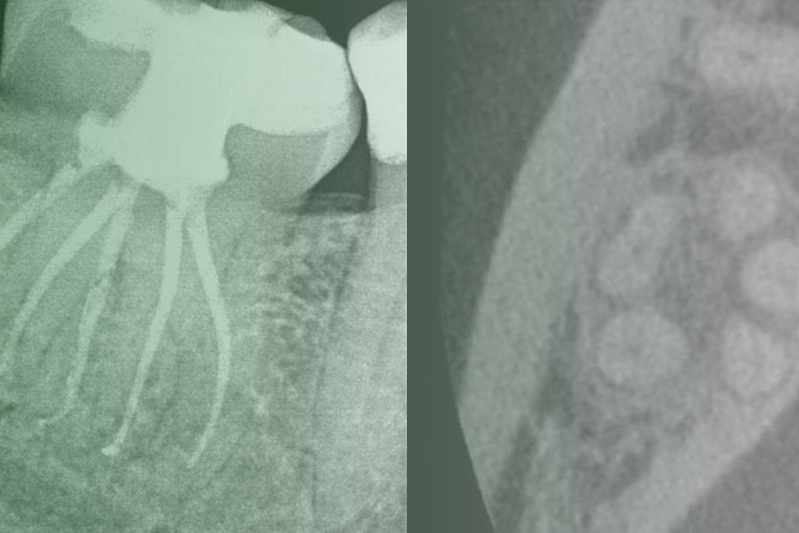

Клинический случай. Эндодонтия

03 марта 2020